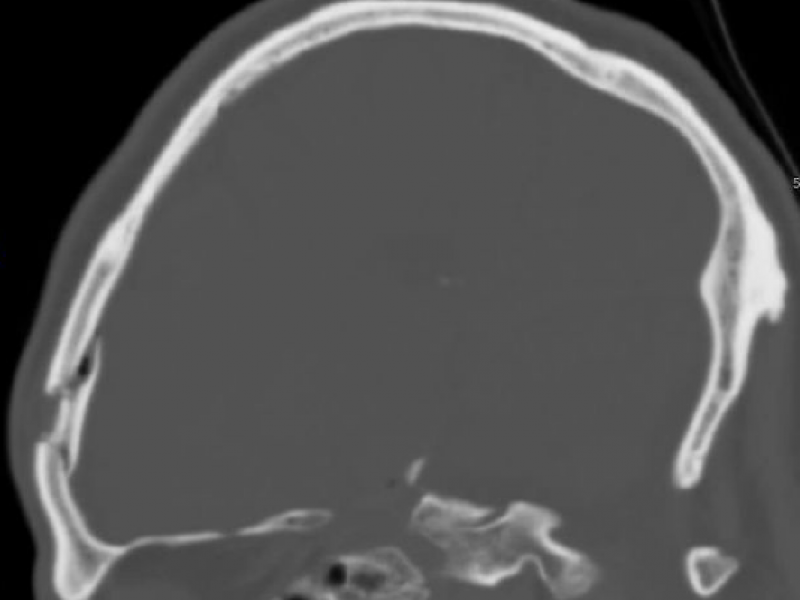

What's the Diagnosis? By Loran Hatch, DO

August 21 2019

A 60 yo M presents to the ED for head trauma. He reports